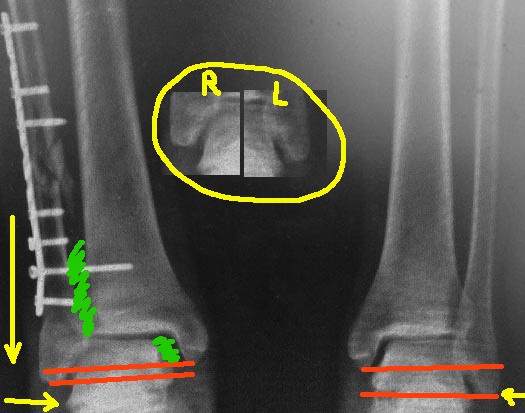

Я немного порисовал на вашем рентгенснимке, чтобы было понятно. теперь

несколько мыслей вслух.

1. Лодыжка укорочена, это видно на прямой проекции, особенно в

сравнении со здоровой ногой - красным нарисовано нормальное

соотношение длины лодыжек у данного пациента (на здоровой ноге) и

укорочение на оперированной. По центру картинки - фрагмент

рентген-снимка, где видно расстояние от верхушки наружной лодыжки до

таранной кости. На травмированной ноге оно значительно больше, за счет

укорочения. Поэтому:

2. Пластину убрать. Выполнить косую остеотомию, видимо на уровне

перелома, т.к. ниже малоберцовая кость будет наверняка фиксирована

рубцовыми тканями в межберцовой зоне, и выраженной подвижности вы не

получите.  Зачистить межберцовую зону, зайдя по переднему краю

малоберцовой кости (зеленое на картинке), убрать рубцовые ткани, чтобы

поставить лодыжку на место. Если есть необходимость, то сразу

выполнить доступ и с антеро-медиальной стороны, из небольшого разреза.

Зайдя за внутренюю лодыжку в сустав, вычистить весь фиброз оттуда

(зеленое на картинке), под контролем ЭОП убедиться, что руками

таранная кость легко прижимается к внутренней лодыжке. На ЭОПе

смотреть не ликвидацию подвывиха, а эффективность прижатия таранной

кости к внутр. лодыжке. Если не встает - значить не всё вычистили.

Лезьте снова.